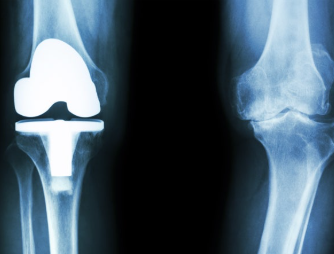

1. 무릎 인공관절 수술이란?

무릎 인공관절 수술은 퇴행성 관절염이나 관절 손상으로 인해 정상적인 생활이 어려운 분들을 위해 손상된 관절을 금속 또는 플라스틱 인공관절로 치환하는 수술입니다.

- 일반적으로 치환술이라고도 하며, 전치환(전체 교체)과 부분 치환술로 나뉩니다.

7. 무릎 인공관절 수명과 재수술 여부

- 평균 15~20년 수명 (일상생활 기준)

- 50대 중반에 수술할 경우, 80세 전후에 재수술 고려 가능성 있음